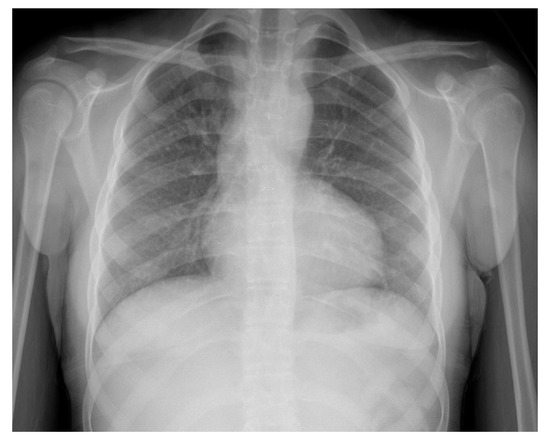

Her ECG showed sinus rhythm and left ventricular hypertrophy (Figure 5). Chest X-Ray showed cardiomegaly with increased bronchovascular markings (Figure 6). Echocardiogram showed mildly dilated and hypertrophied RV with a diastolic septal flattening, normal-sized normal left ventricle, and normal biventricular systolic function. There was severe pulmonary valve regurgitation with mild stenosis of the RV to pulmonary artery conduit with a mean gradient of 40 mmHg. Her CT angiogram (Figure 7) showed no residual ventricular septal defect and mildly dilated aortic root 18 × 17 × 14 mm), moderately to severely dilated ascending aorta (29 × 27 mm) and arch of aorta (27 × 26 mm). Right (11 × 9 mm) and left (15 × 11 mm) pulmonary arteries were mildly dilated. There are stenosis of the right pulmonary artery in distal branches. There were no large MAPCAs. She remained on aspirin only. Cardiac catheterization showed dilated branch pulmonary arteries but stenosis of right branch pulmonary arteries (Figure 8) and hemodynamics revealed normal total PVR. The lung perfusion study showed 65% of flow to left lung compared to 35% to right lung. As there was increased blood flow to the left lung compared to the right lung, changes in the distal pulmonary vasculature were significant in the left lung as shown in Figure 9A compared to right pulmonary vasculature (Figure 9B).

Figure 6. Chest X-ray (Case-2). Cardiomegaly, left lower lobe atelectasis.